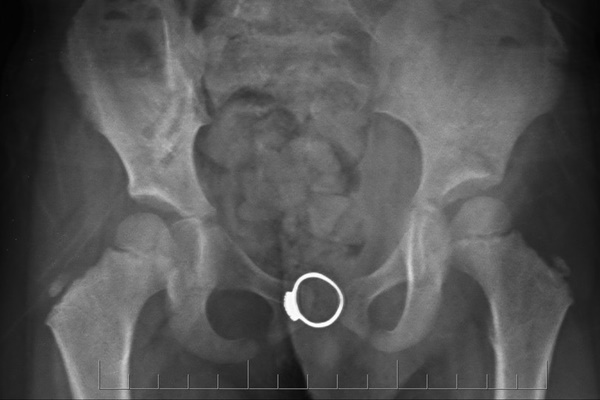

Hình ảnh X-quang thấy rõ chiếc nhẫn trong vùng kín của trẻ. Ảnh: BVCC.

Tại đây, qua thăm khám, BSCKI Nguyễn Văn Hưng, Trưởng khoa Sản 2, cho biết bệnh nhi vào viện trong tình trạng khỏe mạnh, không sốt, không chảy máu âm đạo, âm đạo có tiết ít dịch. Hình ảnh siêu âm thấy có hình ảnh khối tăng tâm trong âm đạo. Bé M. được chỉ định chụp X-quang, kết quả cho thấy hình ảnh một dị vật kim loại hình nhẫn trong âm đạo, độ sâu 4,8 cm.